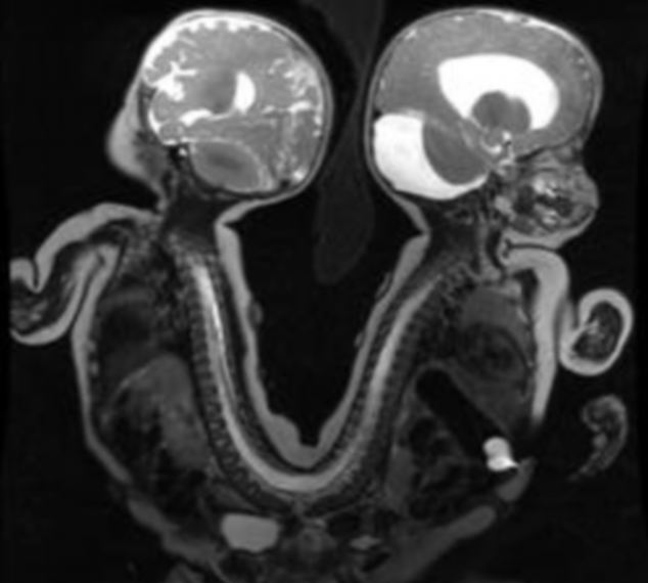

Τα οχτώ μηνών αδέλφια που γεννήθηκαν στο Memphis του Tennessee ήταν ενωμένα στο πίσω μέρος της λεκάνης καθώς και στο γαστρεντερικό σωλήνα τους με αποτέλεσμα να μην μπορούν να βλέπουν ο ένας τον άλλον.